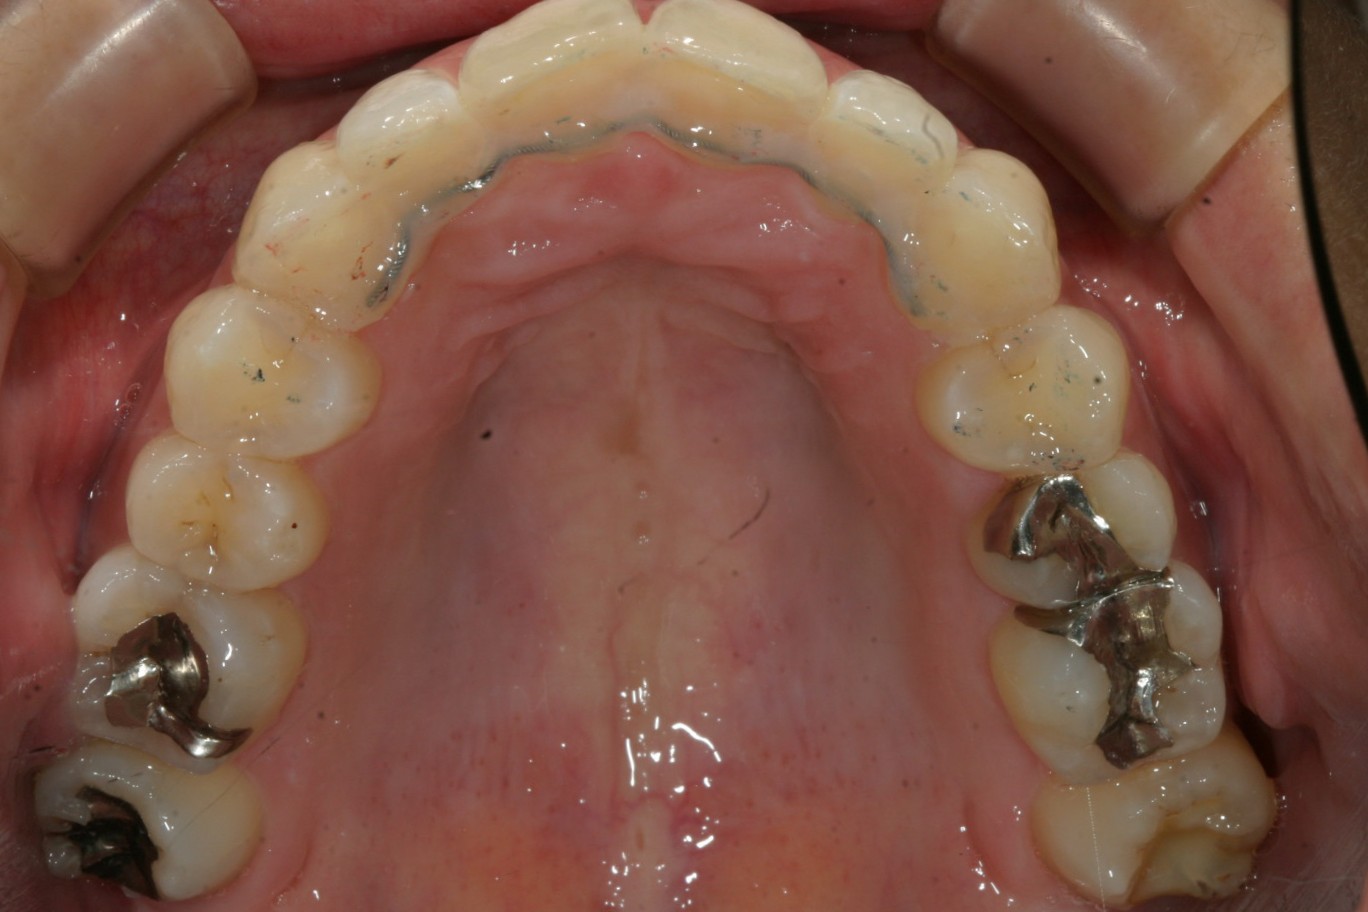

アーチを拡大する事によりこの様に綺麗に改善しました。 非抜歯ですよ。

今回の症例は非抜歯で過度な叢生と出っ歯を何処まで改善できるかと言う事で来院されました。

先ずはいつものようにアーチフォームの拡大を行い、それと出っ歯改善の為のIPR(歯と歯の隙間を削る)を行いました。

ご覧くださいインビザラインで非抜歯でもここまで出来ると言う症例となりました。